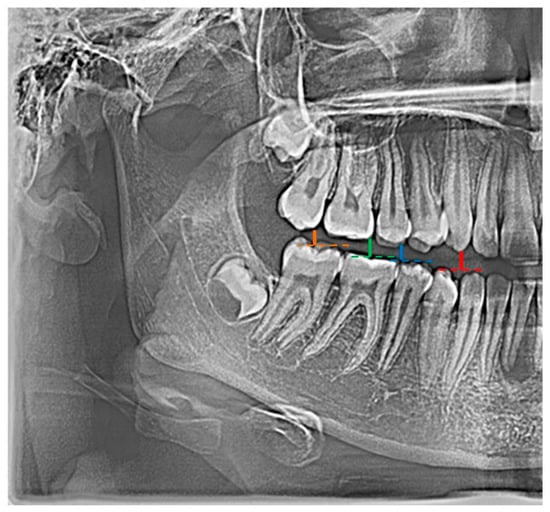

In the conducted research, an original and authored set of 21 indicators was used, i.e., distinctive tooth and bone parameters, which were developed in the form of mathematical proportions X01–X21 by Zaborowicz [] (Figure 1).

Figure 1.

Example graphical representation of indicators: X01 (color: red |C13C43|; blue |C15C45|), X02 (color: red |C13C43|; green |C16C46|), and X03 (color: red |C13C43|; orange |C17C47|).